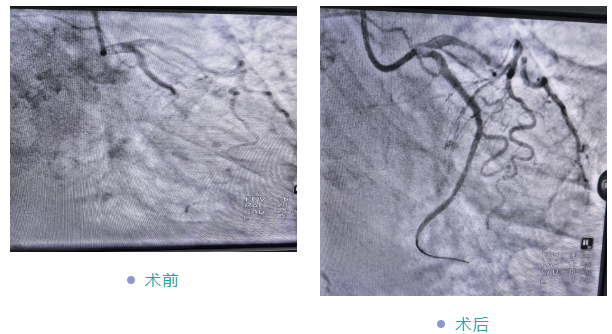

• 字体

据悉,该患者因“反复胸痛1年,再发加重10天”入院,经初步检查确诊为冠心病。考虑到患者年事已高、身体耐受度有限,传统治疗风险较高,心血管内科团队高度重视,立即组织科内讨论,全面评估其心肺功能、基础疾病及手术风险,经充分研讨后制定了个体化微创介入方案——先通过冠脉造影明确病变情况,再视结果实施支架植入。

手术当日,在副院长黄修平与心血管专科医生李昊弋的精准操作、默契配合下,冠脉造影与支架植入顺利完成,全程平稳有序。术后,患者胸痛症状明显缓解,生命体征稳定;在医护团队的精心照料与个体化康复指导下,次日即可下床行走,精神状态显著改善,目前已康复出院。